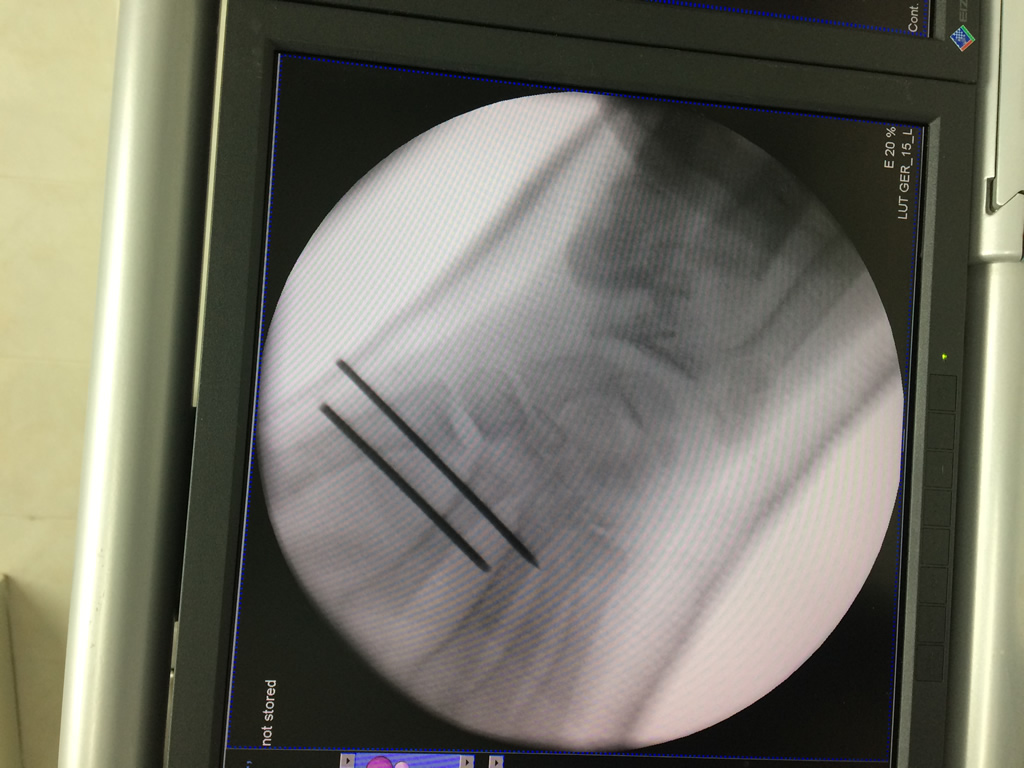

Cirugías de Codo - Cirugías de Muñecas y Manos

Los procedimientos más comunes en cirugía de la mano son aquellos destinados a reparar traumatismos, incluyendo lesiones de tendones, nervios, vasos sanguíneos, y articulaciones; huesos fracturados; y quemaduras, cortes, y otros daños de la piel.